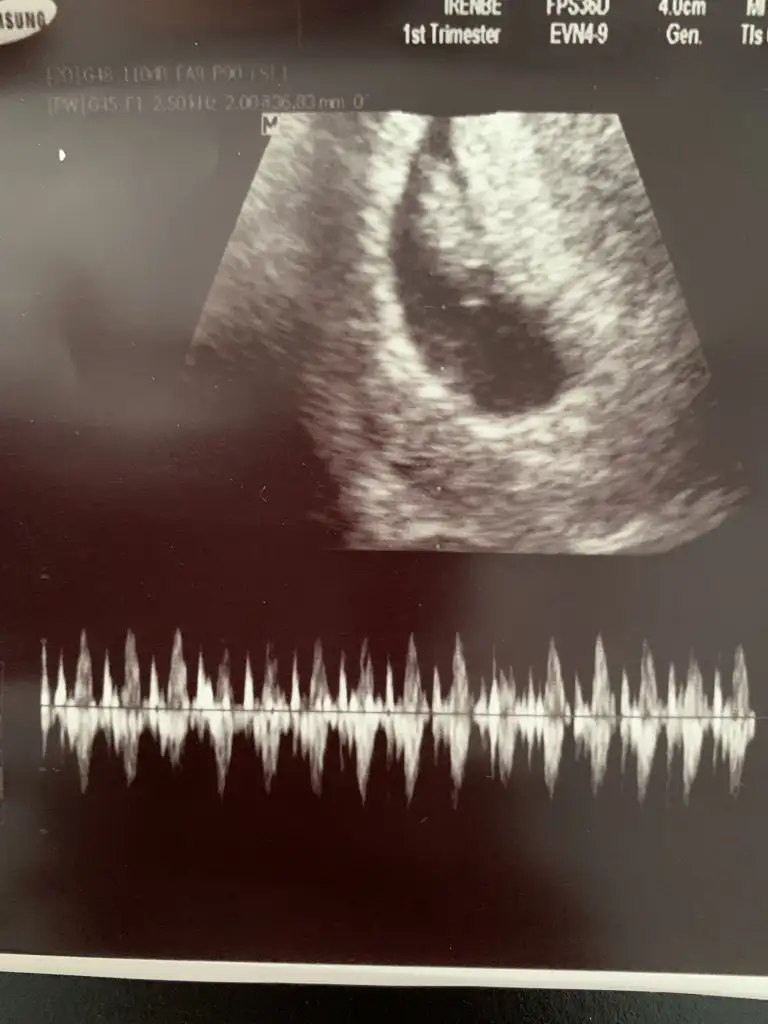

kuzuuuu iki tosun paşa bunlarŞimdi ikisinin ayrı görüntülerini de atıyorum bi de böyle bakVajinal usg

kuzum görüntüyü düz çekip atar mısın, bebek sol alttaki mi? o sanki yolk sac gibiSelam 6+3 teki foto ile ben de geldim